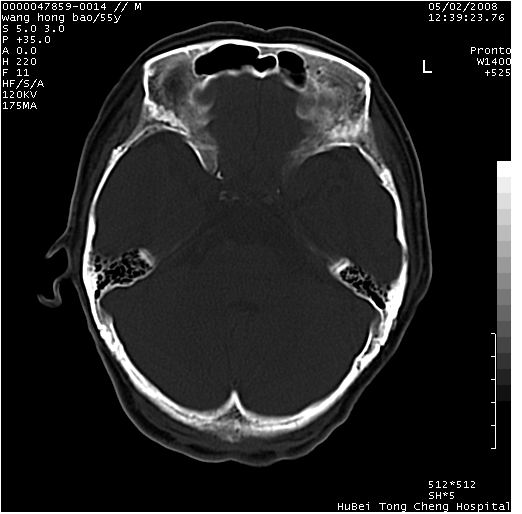

以下是引用dyqct在2008-5-3 23:36:00的发言:[br]桥前池区可疑蛛网膜囊肿。其它未见明显异常。建议做mri。

以下是引用qiushi在2008-5-4 10:10:00的发言:[br]鞍上池前缘突出影为双侧额叶直回;箭头所指为双侧正常之人字缝.[br]桥前池区可疑表皮样囊肿或蛛网膜囊肿,必要时mri

以下是引用zjzjr在2008-5-4 14:50:00的发言:[br]桥前池区可疑蛛网膜囊肿。其它未见明显异常。建议做mri。